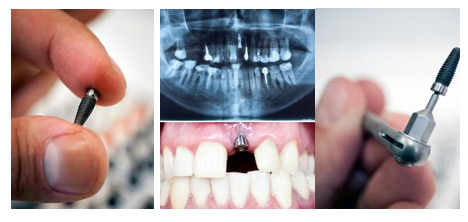

种植体1折起 颠覆底价

瑞典诺贝尔、美国皓圣、瑞士ITI等欧美种植体品牌一直是种植界的翘楚,凭借出色的初期稳定性、生物相容性、高成功率成为缺牙患者更信赖的品牌,但价格昂贵,一颗植体就要上万元,很多条件一般的顾客负担不起。

正逢康贝佳口腔集团9周年庆典,感谢沈城市民的一路同行,康贝佳携手百强厂商共同推出大幅让利活动。多种欧美高端种植体1折起,诺贝尔植体还可享全球联保、终身质保。